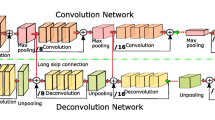

Lung cancer represents one of the most common and lethal types of cancerous pathologies and lung nodules are an early indicator for pulmonary cancer. Hence, a precise and reliable segmentation of lung nodules could enhance early diagnosis and therapy and thus, increase patients’ survival rates. This work proposes a modified 3D-Res2Unet, combining an Unet-style neural network architecture with residual blocks and attention mechanisms. This network was tested on the publicly available LUNA16 CT dataset and achieved on average 91.27 ± 6.49 %. Therefore, the proposed method indicates state-of-the-art performance and could represent an important tool for early diagnosis of lung cancer.

**ao Z, Liu B, Geng L, Zhang F, Liu Y. Segmentation of lung nodules using improved 3D-UNet neural network. Symmetry (Basel). 2020;12(11):1787.

Keetha NV, Annavarapu CSR et al. U-Det: a modified U-Net architecture with bidirectional feature network for lung nodule segmentation. ar**v preprint ar**v:2003.09293. 2020.

Ronneberger O, Fischer P, Brox T. U-Net: convolutional networks for biomedical image segmentation. CoRR. 2015;abs/1505.04597.

Çiçek Ö, Abdulkadir A, Lienkamp SS, Brox T, Ronneberger O. 3D U-Net: learning dense volumetric segmentation from sparse annotation. 2016.